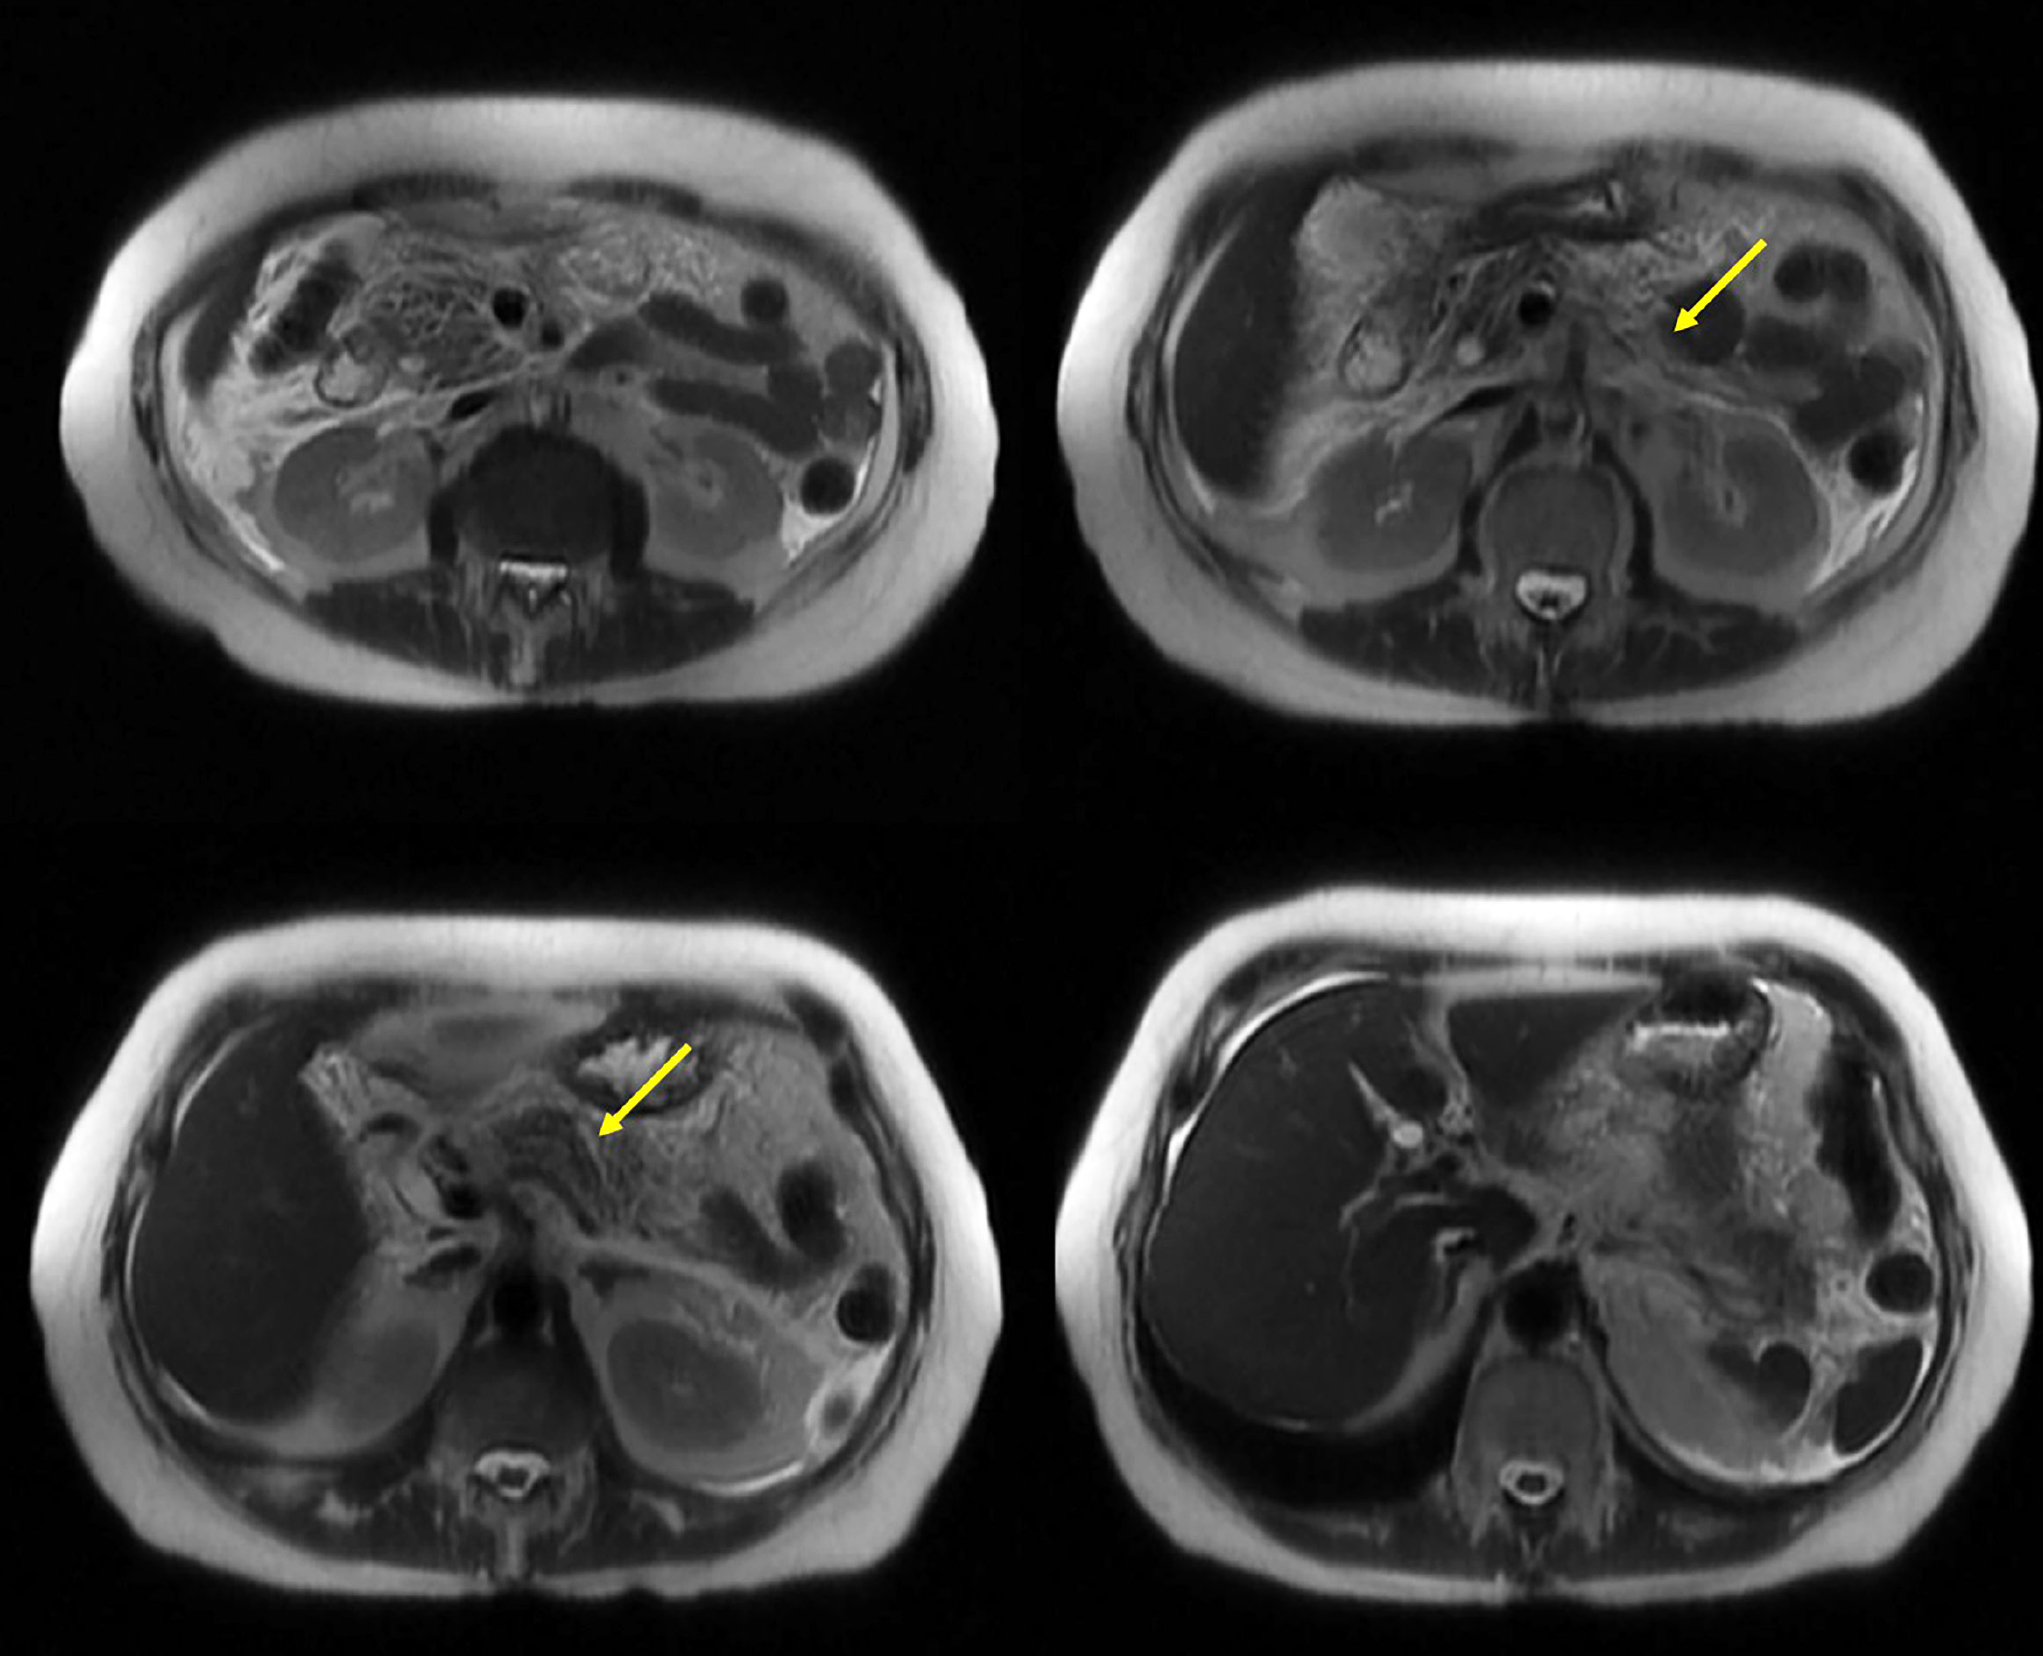

La inflamación del páncreas, llamada pancreatitis, es un motivo de consulta común, y es uno de los más representativos cuando el dolor abdominal es el motivo de consulta para acudir a una sala de emergencia; representa un alto costo para todo el sistema de salud, pues solo uno de cada tres pacientes cursa con pancreatitis moderada a grave, con un aumento significativo de morbimortalidad y tasa de complicaciones. Actualmente, las principales etiologías incluyen causas obstructivas de origen biliar o no biliar por reflujo y ausencia de flujo de enzimas al intestino que se activan en el parénquima degradándolo, el alcoholismo y la hipertrigliceridemia son mecanismos relacionados con la toxicidad celular luego del metabolismo de estas moléculas. La pancreatitis inducida por fármacos es una afección rara relacionada con antibióticos, analgésicos y antidepresivos. El deferasirox es un quelante del hierro especialmente utilizado en pacientes que necesitan múltiples transfusiones para evitar la sobrecarga de hierro. Ha sido poco correlacionado con el desarrollo de pancreatitis, aunque existen datos que podrían corroborarla; adicionalmente la farmacéutica responsable de su producción incluye esta entidad como una posible complicación en los aspectos técnicos. Este artículo presenta el caso de una paciente de 71 años de edad que desarrolló pancreatitis moderada a grave sin complicaciones importantes. Los médicos descartaron las causas más frecuentes de pancreatitis, por lo que concluyeron que el agente desencadenante fue el quelante del hierro deferasirox.